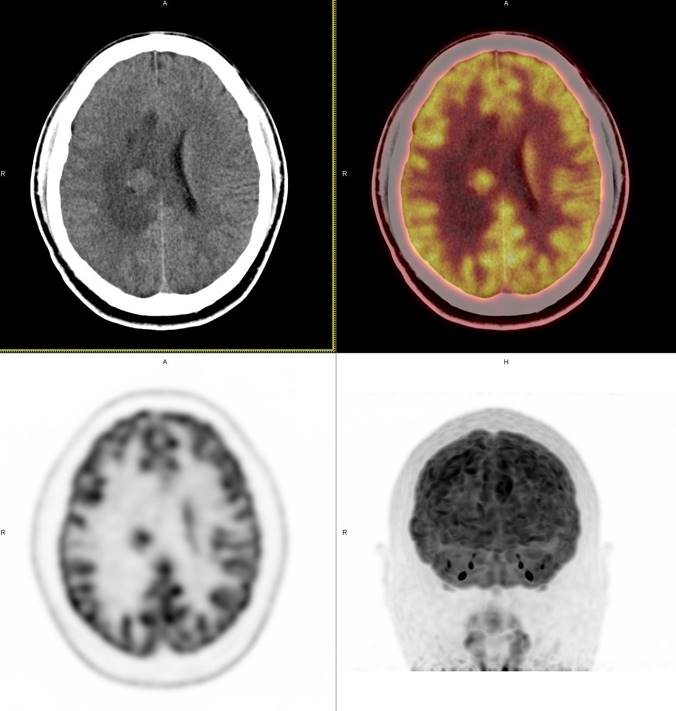

PET/CT影像圖

圖2

PET/CT檢查

影像診斷: 右側(cè)側(cè)腦室旁腦實質(zhì)內(nèi)結節(jié),代謝異常增高(SUVmax 12.13),伴瘤周水腫。

病理診斷:腦膜瘤二級

PET/CT鑒別診斷

正電子發(fā)射計算機斷層(positron emission tomography,PET)是一種分子成像技術,PET 應用 18F-FDG等顯像劑可顯示人體內(nèi)細胞、分子或者基因水平的生物學、病理學過程,進一步實現(xiàn)疾病早期定量與定性診斷。PET/CT使形態(tài)影像學與功能影像學得到了良好的結合,更有利于對腦膜瘤進行全面的評價。既往研究發(fā)現(xiàn),18F-DG PET/CT對診斷WHOⅠ、Ⅱ級腦膜瘤具有較高的敏感度,F(xiàn)DG攝取可用于評估腦膜瘤的腫瘤增殖情況,以此達到鑒別腦膜瘤的良、惡性的目的。有學者統(tǒng)計,WHOⅡ、Ⅲ級與 WHOⅠ級的平均標準化攝取值(standardized uptake value,SUV)分別為 2.51 (1.36,3.66)和 0.42 (0.12,0.73),WHOⅡ、Ⅲ級腫瘤與正常組織比率(T/N比率)存在差異,WHOⅡ級腦膜瘤的 SUVmax和最大T/N比率顯著高于 WHOⅠ級腦膜瘤。SUV和T/N比率對高級別腦膜瘤的診斷有較高的特異度。

此例,PET/CT全身檢查不僅排除了轉(zhuǎn)移瘤的可能性,增高的SUV值無創(chuàng)地鑒別腦膜瘤的良惡性,充分體檢PET/CT大視野、形態(tài)與功能影像結合的優(yōu)勢。